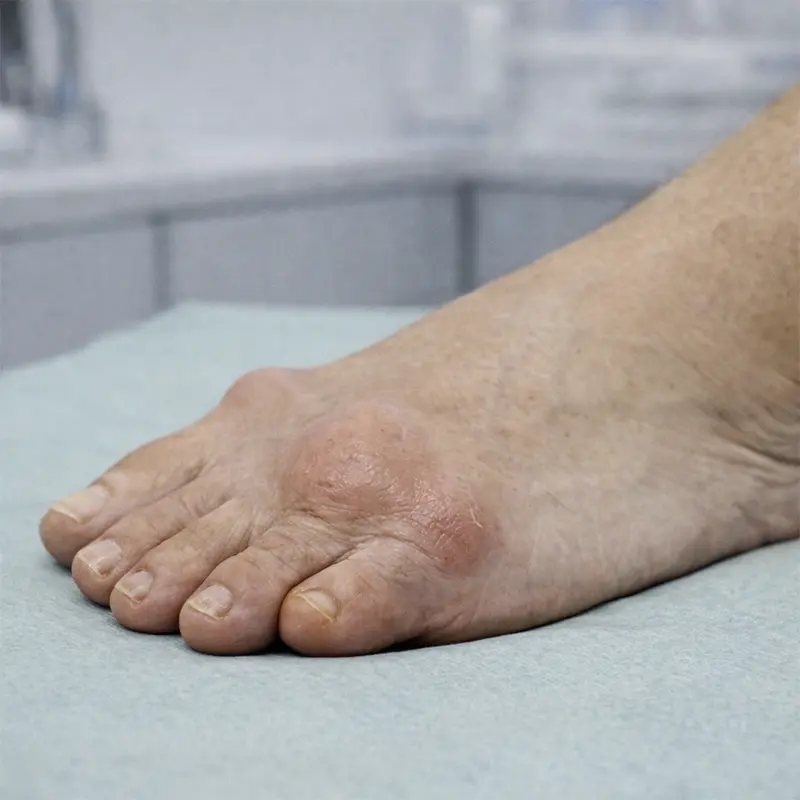

Cirugía de

deformidades

del antepié

El antepié concentra muchas de las patologías quirúrgicas más habituales. Son problemas que suelen avanzar con el tiempo y que, cuando generan dolor o deformidad progresiva, pueden limitar de forma importante la vida diaria. Nuestra especialización quirúrgica, buscando la mínima invasión y la rápida recuperación, incluye, entre otras, la cirugía de:

- Juanetes (hallux valgus).

- Metatarsalgia.

- Neuroma de Morton (radiofrecuencia o cirugía).

- Deformidades de los dedos (dedo en martillo, dedo en garra, dedo en mazo, dedo crossover).

- Reconstrucción del antepié.

- Hallux limitus y hallux rigidus (artrosis del dedo gordo del pie).

En muchos de estos casos el paciente ha probado previamente plantillas, cambios de calzado o tratamientos conservadores. Cuando la deformidad progresa o el dolor persiste, la cirugía del pie permite corregir la causa del problema y mejorar la función.